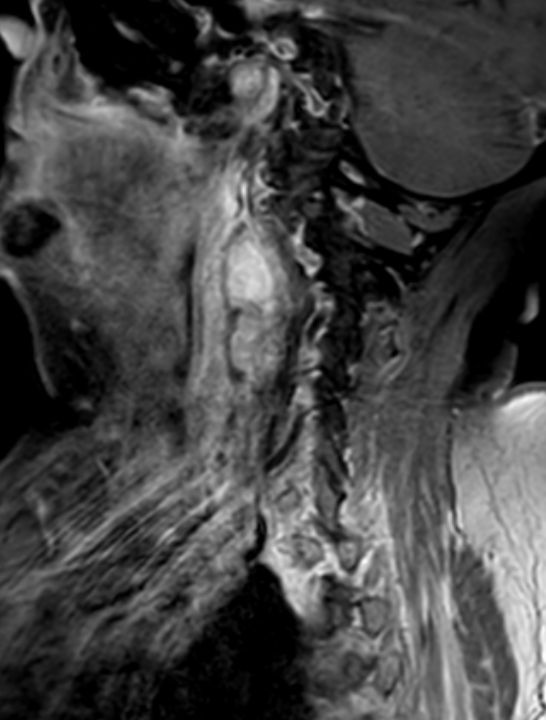

| Diagnostik | 88-jährige Frau mit einer progredientes

Dysphagie. Es besteht eine Raumforderung rechts retropharyngeal. Mukosa intakt.![]()  |